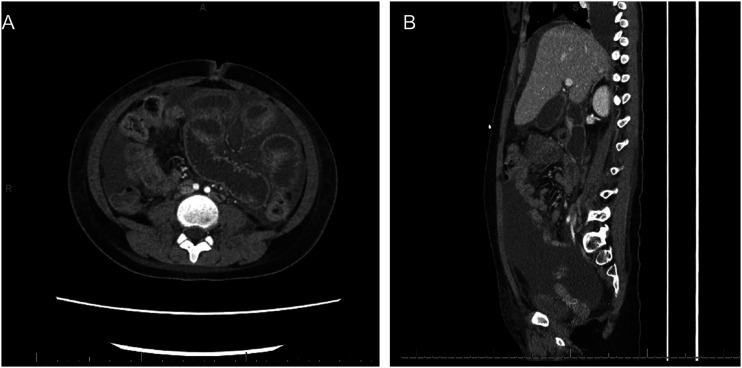

Abstract Image